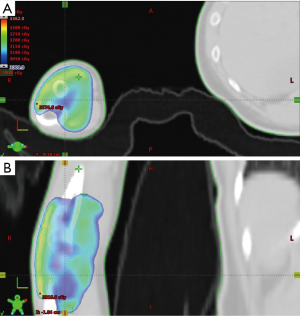

For patients who received operations in our study, they received open synovectomy, arthroscopic synovectomy or both, depending on orthopedic surgeons’ evaluation. Treatment was individualized according to patient characteristics and lesion extension. Adjuvant RT and definitive RT were delivered by linear accelerators with mega-voltage X-rays (4, 6, and 10 MV) using three-dimensional conformal RT or intensity-modulated RT. The median dose of irradiation was 30 Gy (range, 30–40 Gy), in 15 daily fractions of 2 Gy. The clinical target volume of RT included whole synovial space with TGCT/PVNS involvement as well as the cartilage and bony structures invaded by proliferative tissue. An expansion of at least 0.5 cm was delineated as the planning target volume. An example of clinical target delineation and treatment planning was illustrated in Figure 1.